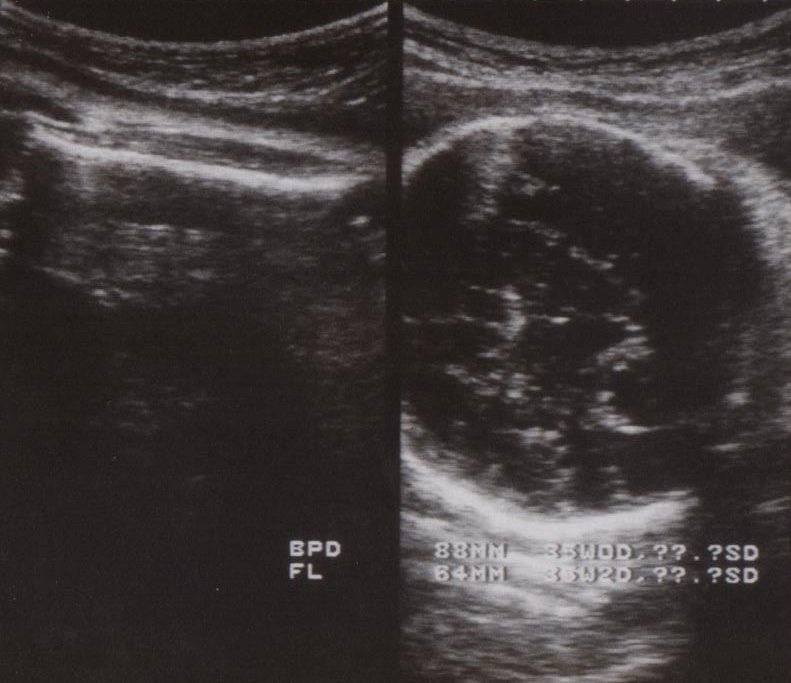

妊娠35週1日 35w1d の超音波 エコー 写真

35週 赤ちゃん 体重 増え方- 妊娠35週の赤ちゃんの様子 顔の筋肉が細かく動くように表情豊かに。 かわいすぎるほほ笑みが見られるのはもうすぐ 35週のエコー写真。 口をすぼめて舌を出しています 画像提供:水野谷つむぎさんの妊娠35週目のエコー写真 赤ちゃんの推定体重2309g 宝物の息子とはおなかのなかで対面してた! エコー写真で出会いからこれまでを振り返る この頃もまだ股関節痛がひどく